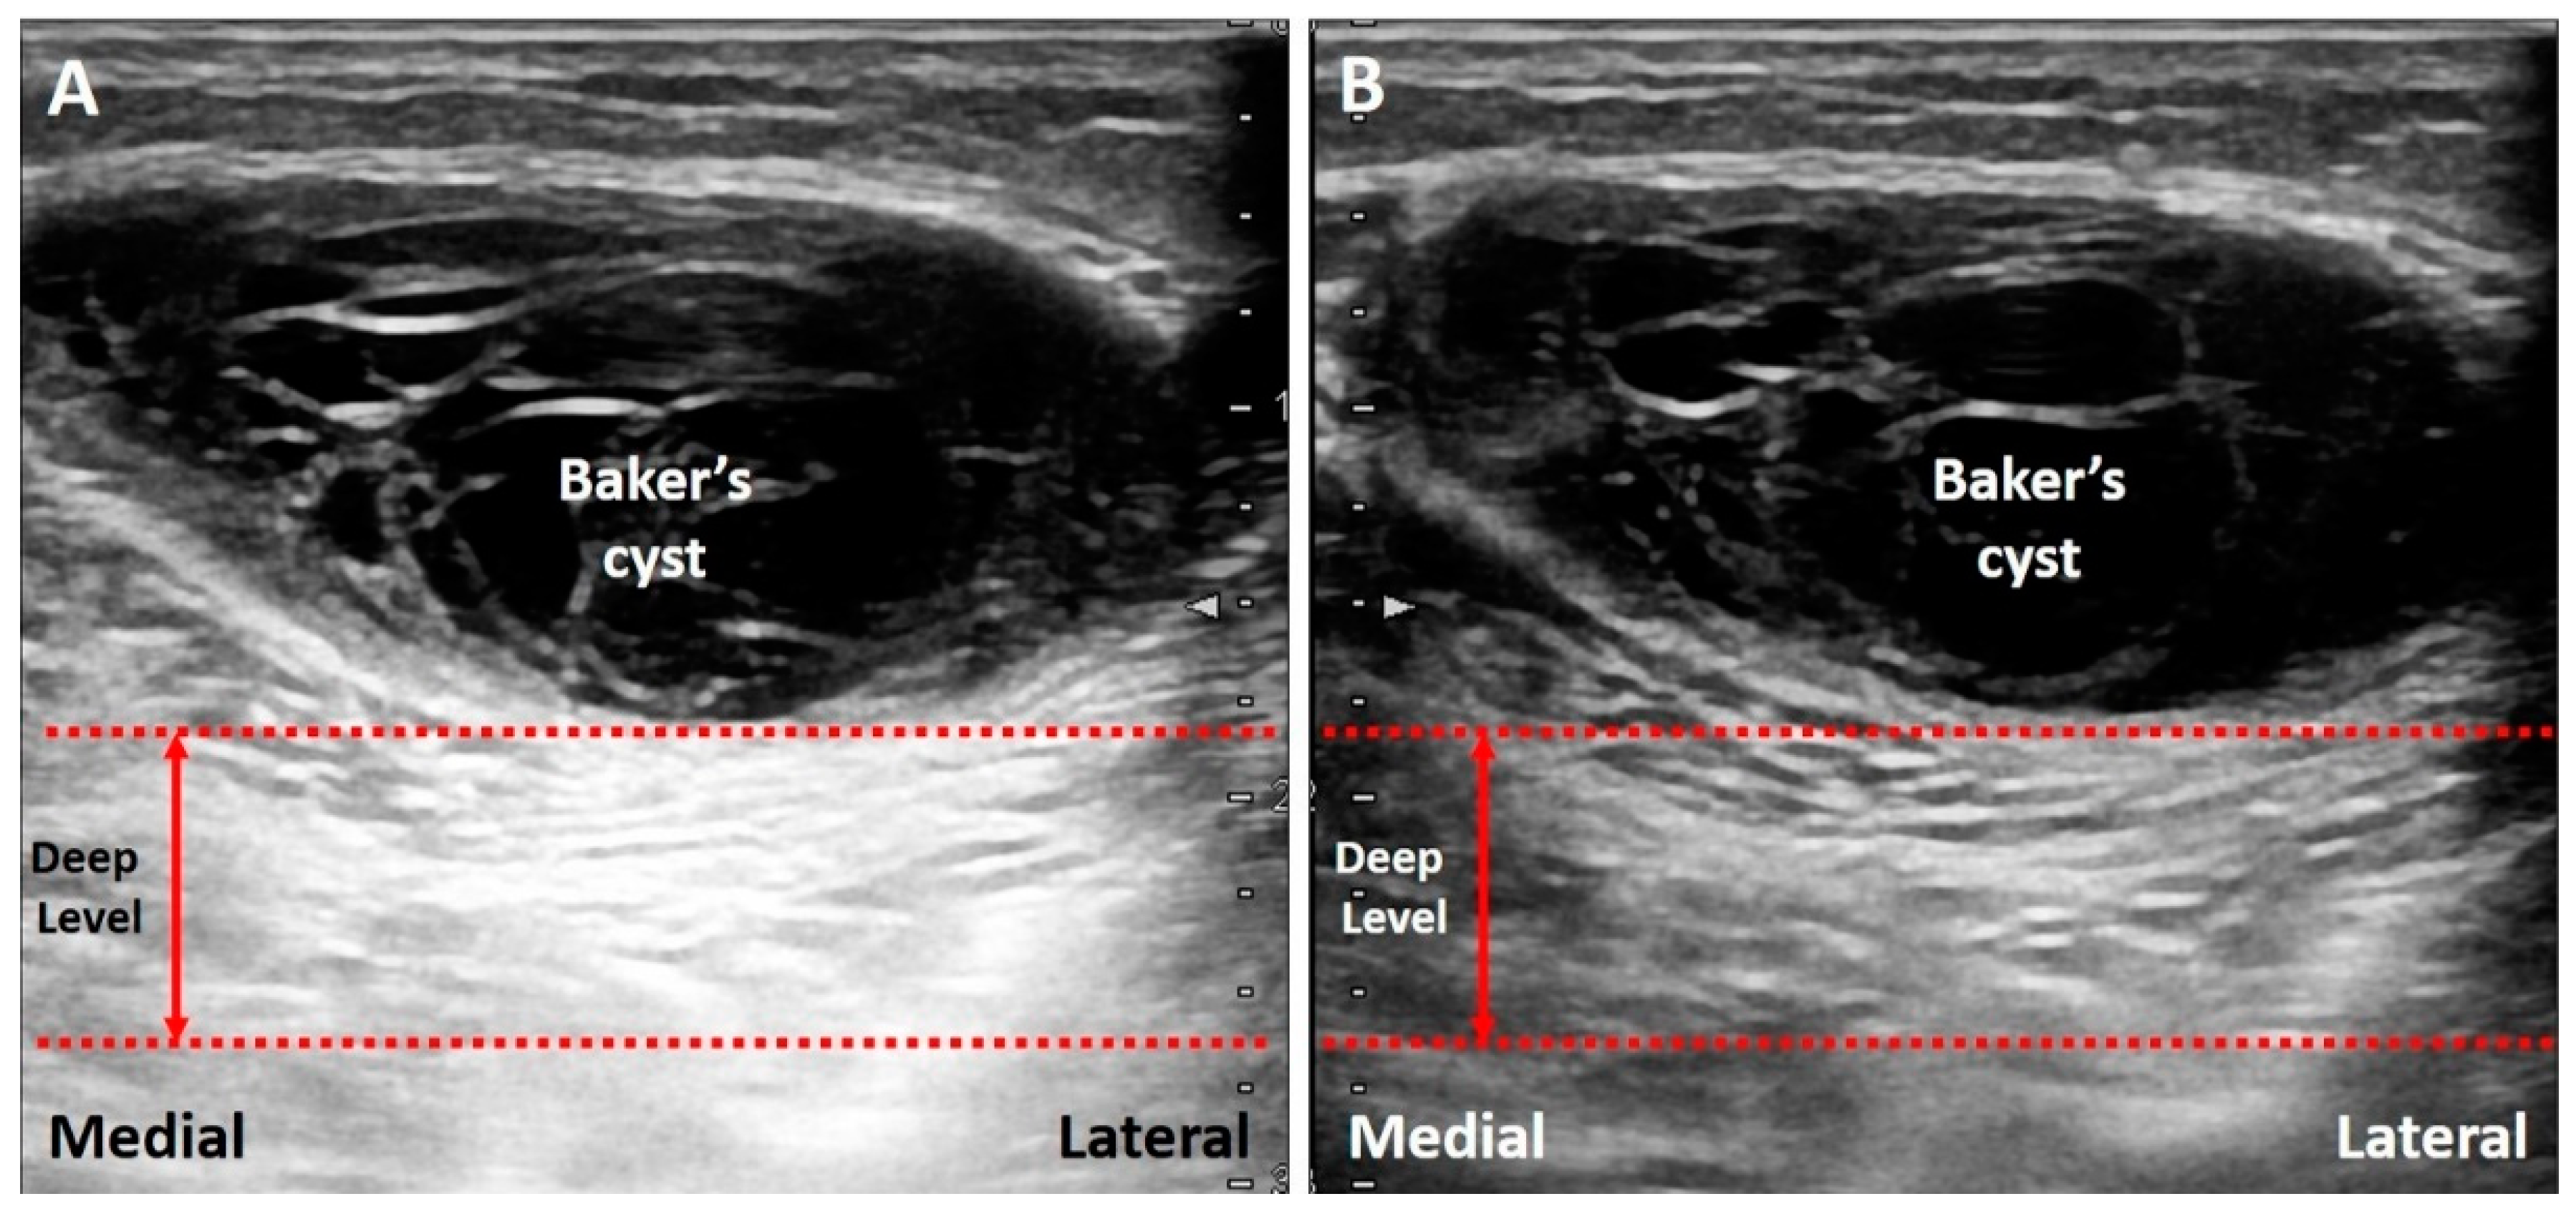

The energy of US waves attenuates through absorption, reflection, or scattering. If the US beam passes through a low-attenuation structure, like effusions or cysts, the signals reflected from the deep structure increase in amplitude compared to the ones from the surrounding tissues (Figure 3A) [17]. In addition, overcompensation of tissue attenuation using the function of time-gain control on the US machine can also result in posterior acoustic enhancement.

Figure 3.

If the US beam passes through a low-attenuating structure, the signals reflected from the deep structure increase in relation to the surrounding tissues (A). The areas deep to a Baker’s cyst (B) and a complete tear of the supraspinatus tendon (C) become hyperechoic because of the posterior acoustic enhancement (and discrepancy of the acoustic impedance between two different tissues). White arrow: artifact due to posterior acoustic enhancement; white arrowhead: cartilage interface sign. MG: medial gastrocnemius muscle. Blue arrows: the projected and reflected US beams. Black circle: the low-attenuation structure.

3.1.2. Clinical Examples

Common pathologies with low-attenuation features include bursitis, ganglion cysts, hematoma, abscess, and joint effusion. For instance, the Baker’s cyst (Figure 3B), communicating with the knee joint, is a common fluid-filled mass located at the popliteal fossa. It is associated with osteoarthritis, rheumatoid arthritis, and meniscus tears. Under US imaging, the anechoic mass is situated between the medial gastrocnemius muscle and the semimembranosus tendon [18]. Tissues deep in the Baker’s cyst appear hyperechoic due to posterior acoustic enhancement. Likewise, in case of a complete tear of the supraspinatus tendon [19], the torn part exhibits effusion. The surface of the humeral cartilage becomes brighter due to increased reflection of the US beam deep to the effusion and marked difference in acoustic impedance between the effusion and humeral cartilage. This presentation is also called the “cartilage interface sign” (Figure 3C) [20]. If a lesion is deep to a low-attenuation structure (Figure 4A), decreasing the gain at the deeper region can reduce posterior enhancement and improve the resolution of the target (Figure 4B).

Figure 4.

The area deep to the Baker’s cyst is hyperechoic, making it difficult to differentiate the echotexture (A). Decreasing the signal gain at the deep level can reduce the posterior enhancement and help in clarification of the echotexture (B). Red dash line: the level deep to the target. Red double arrow: the range of the depth regarding the area highly influenced by the artifact.